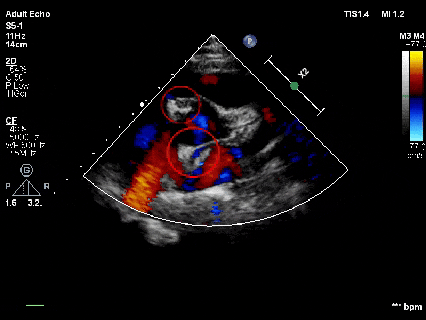

释放后超声

超声下可见室水平和房水平都无残余分流

心脏彩超:心脏超声下可见两个封堵器双盘稳固夹持,无残余分流;

术后1个月心脏超声,房室水平皆无残余分流